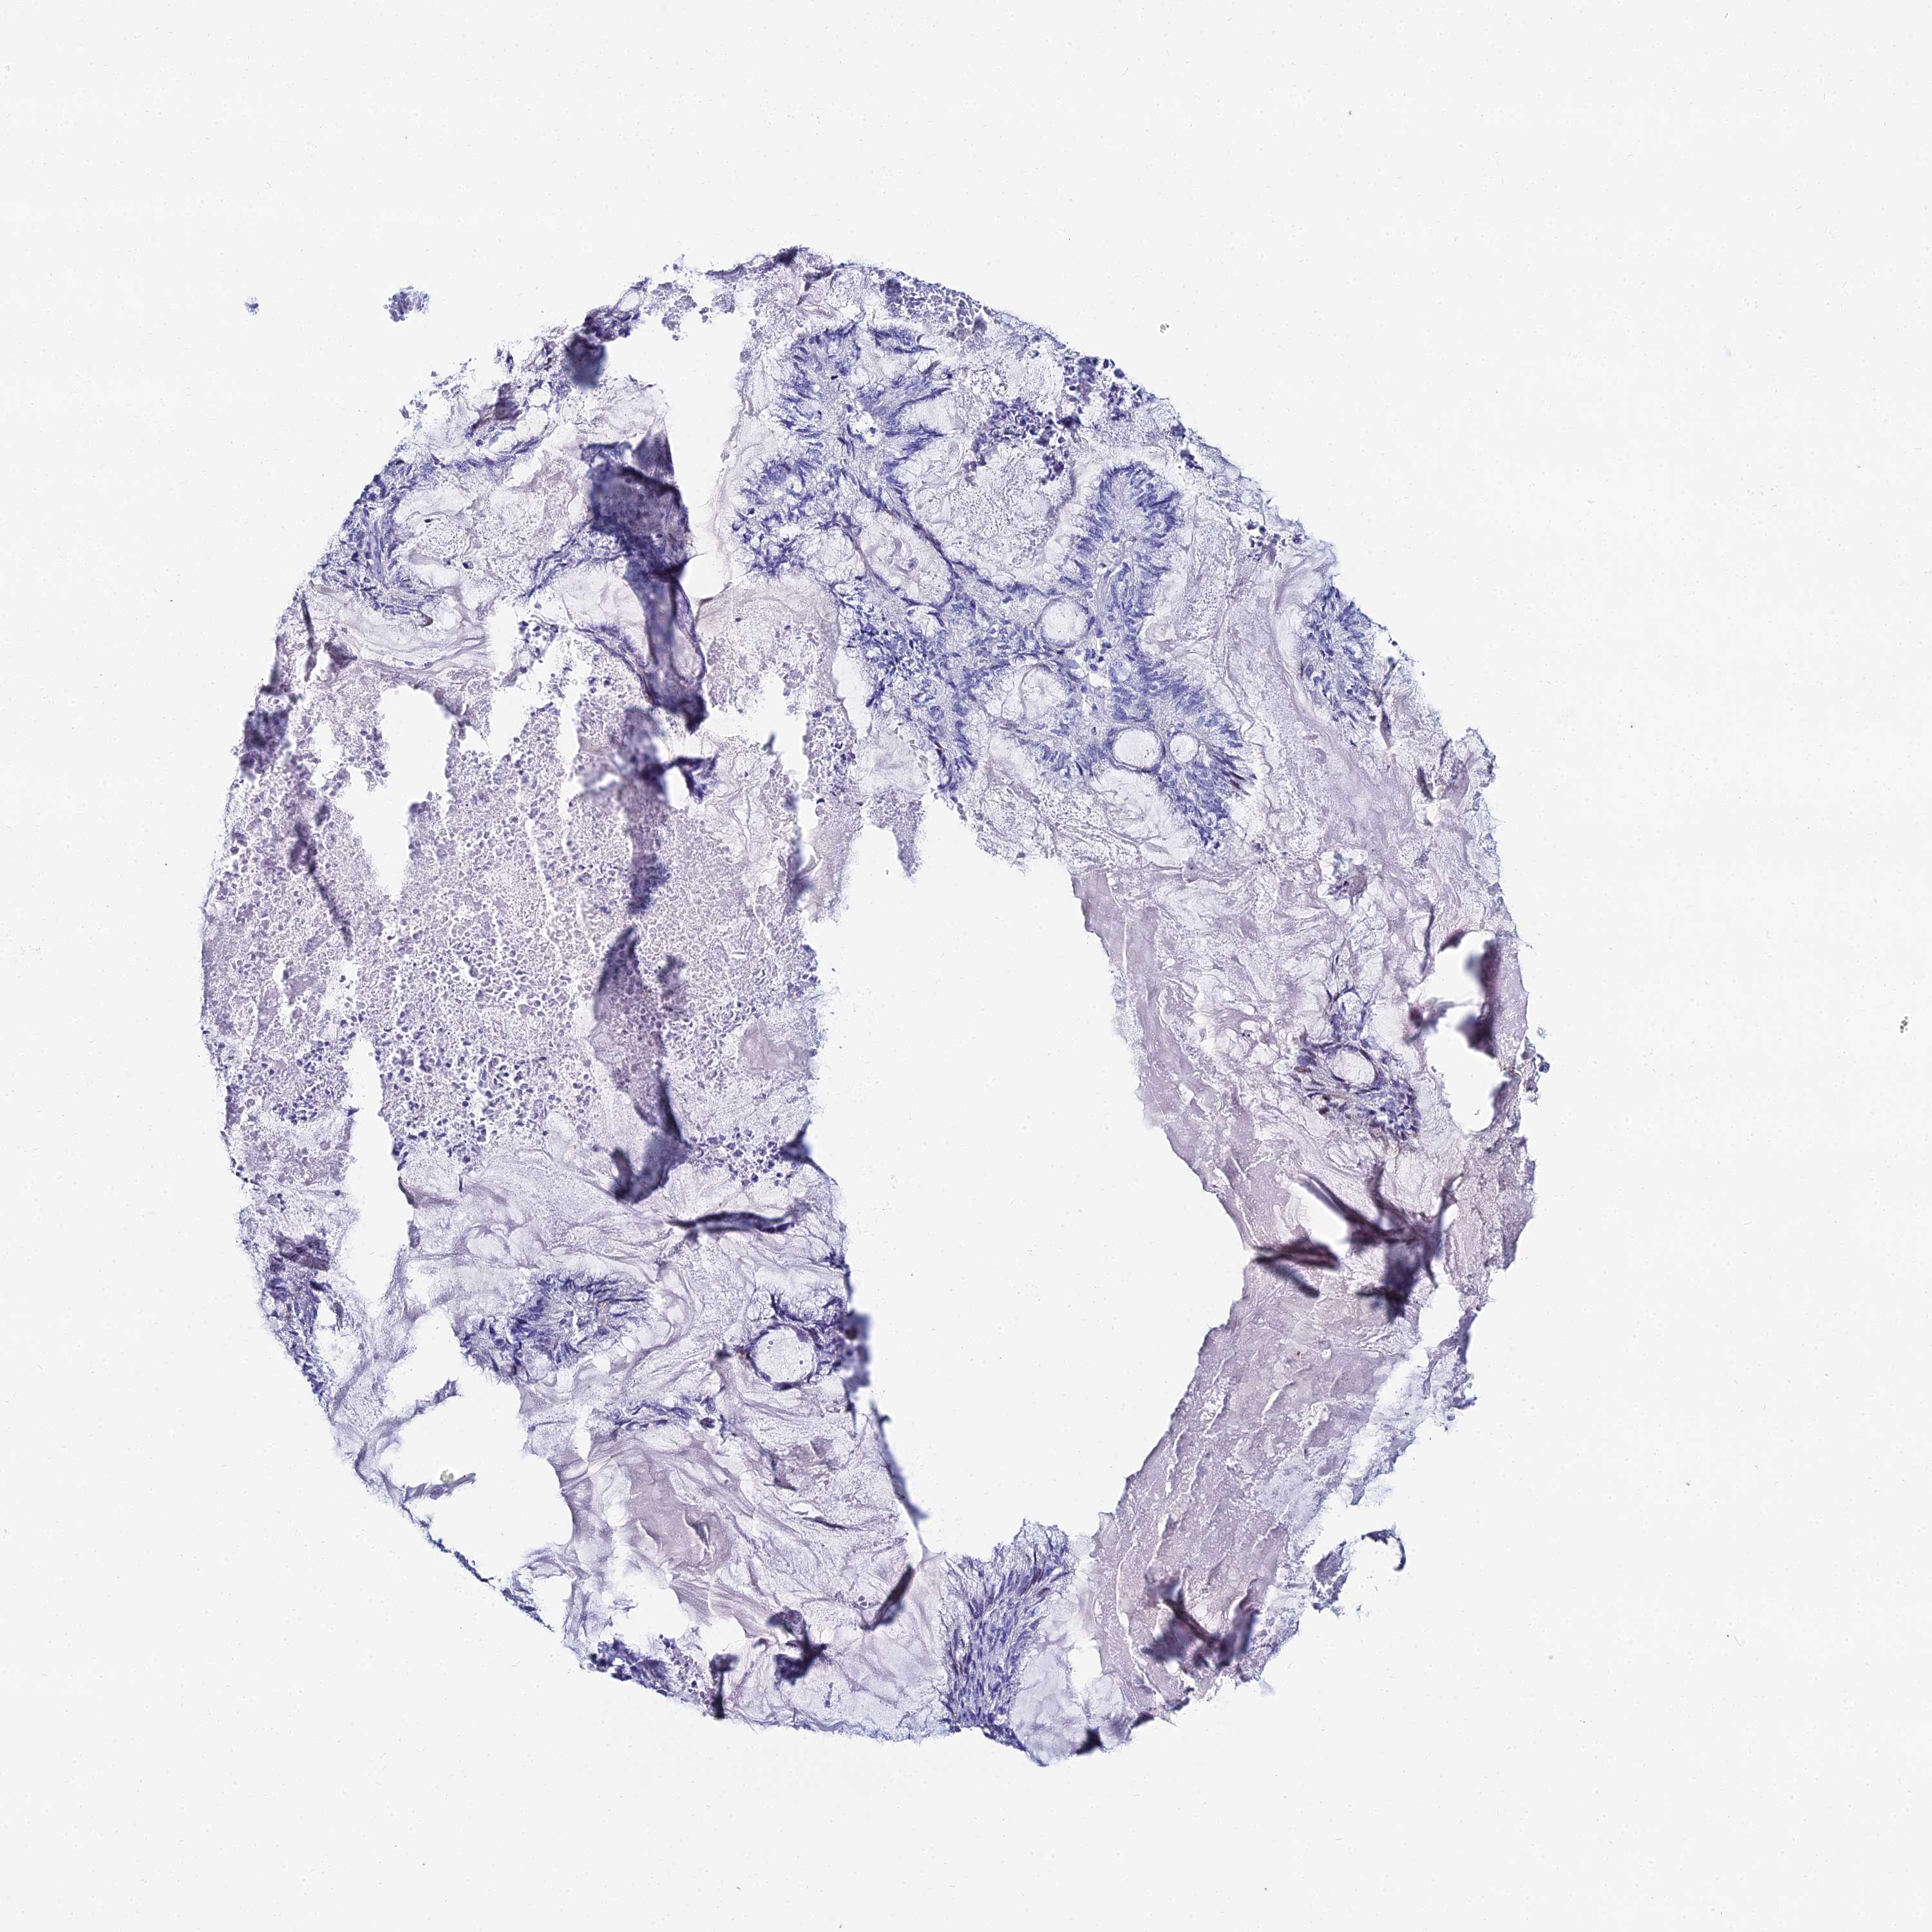

ENDOMETRIAL CANCER - Protein expressioni

A mouse-over function shows sample information and annotation data. Click on an image to view it in a full screen mode. Samples can be filtered based on level of antibody staining by selecting one or several of the following categories: high, medium, low and not detected. The assay and annotation is described here.

Note that samples used for immunohistochemistry by the Human Protein Atlas do not correspond to samples in the TCGA dataset.

Antibody stainingi

Antibody staining in the annotated cell types in the current human tissue is reported as not detected, low, medium, or high, based on conventional immunohistochemistry profiling in selected tissues. This score is based on the combination of the staining intensity and fraction of stained cells.

Each image is clickable and will lead to virtual microscopy that enables deeper exploration of all samples and also displays staining intensity scores, fraction scores and subcellular localization as well as patient and tissue information for each sample.

Antibody HPA043285

Antibody HPA052504

Staining

High

Medium

Low

Not detected

Intensity

Strong

Moderate

Weak

Negative

Quantity

>75%

75%-25%

<25%

None

Location

Nuclear

Cytoplasmic/membranous

Cytoplasmic/membranous,nuclear

Adenocarcinoma, NOS

Adenocarcinoma, metastatic, NOS

Carcinoma, NOS